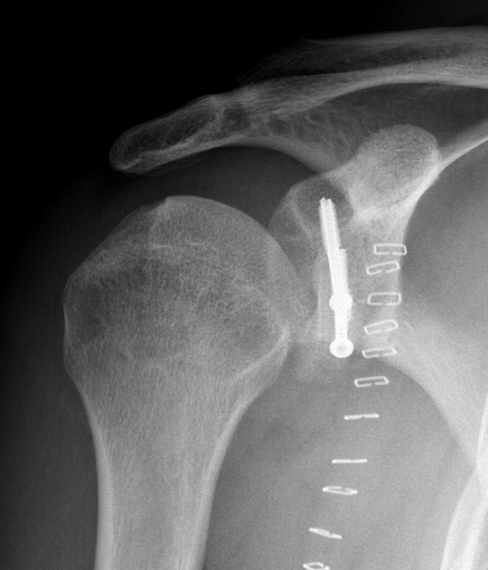

Case 2: Large glenoid defect